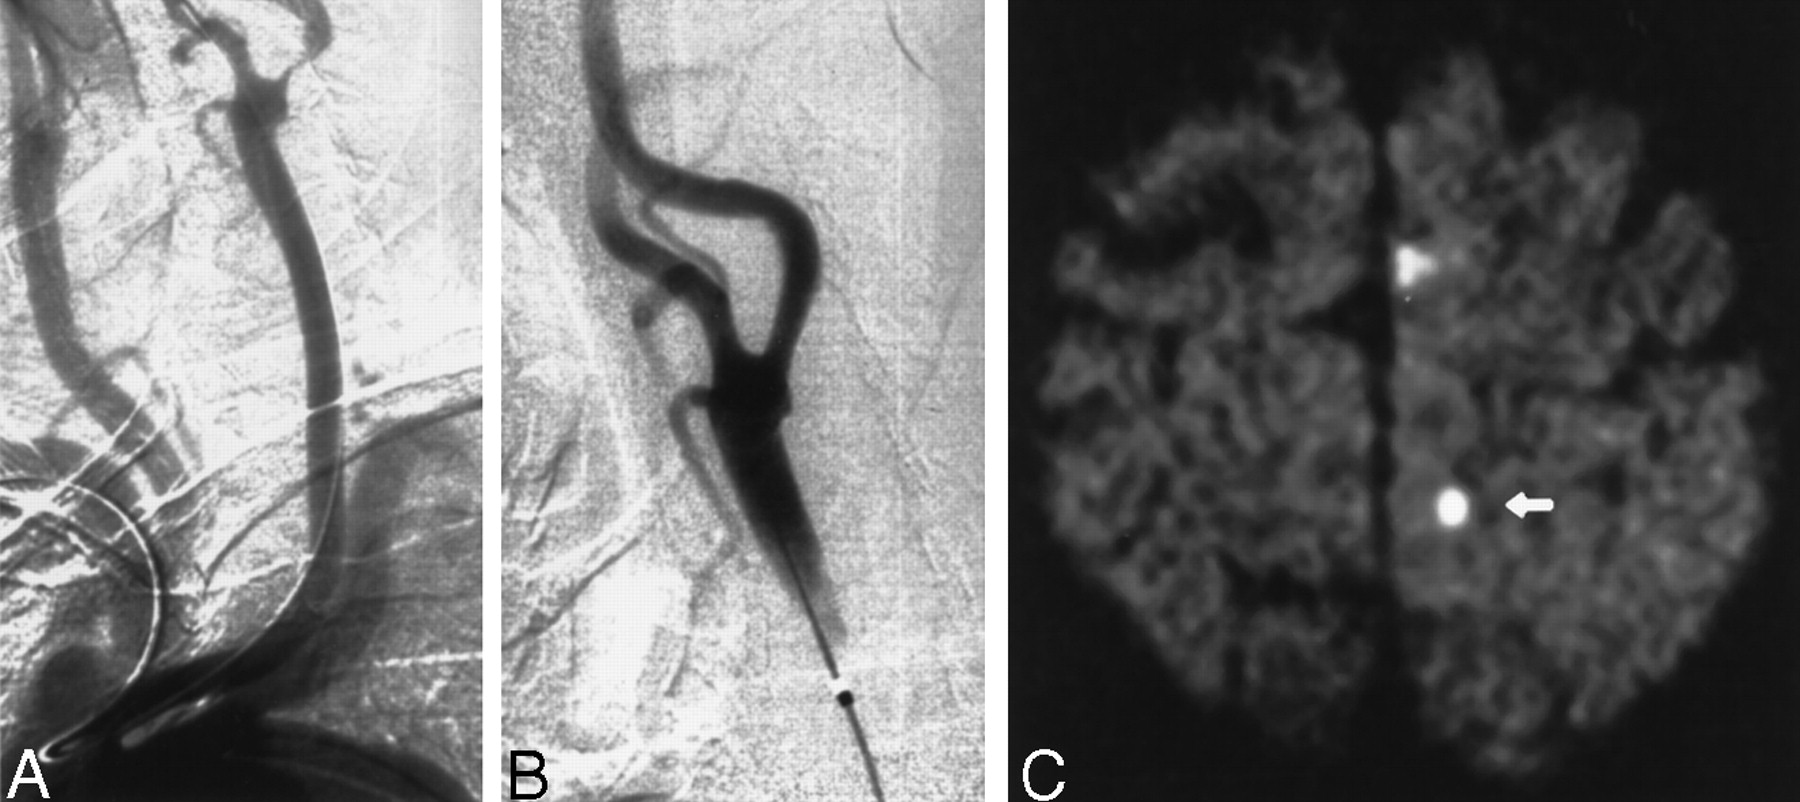

Images obtained in a 70-year-old man with an asymptomatic stenosis of the carotid artery.

A, Right anterior oblique angiogram shows a 94% stenosis of the right ICA.

B, Right anterior oblique angiogram shows the result after stent implantation.

C, Postprocedural axial diffusion-weighted MR image (6000/103/1) shows a new ipsilateral lesion (<5 mm) in the cortical territory of the MCA (arrow).